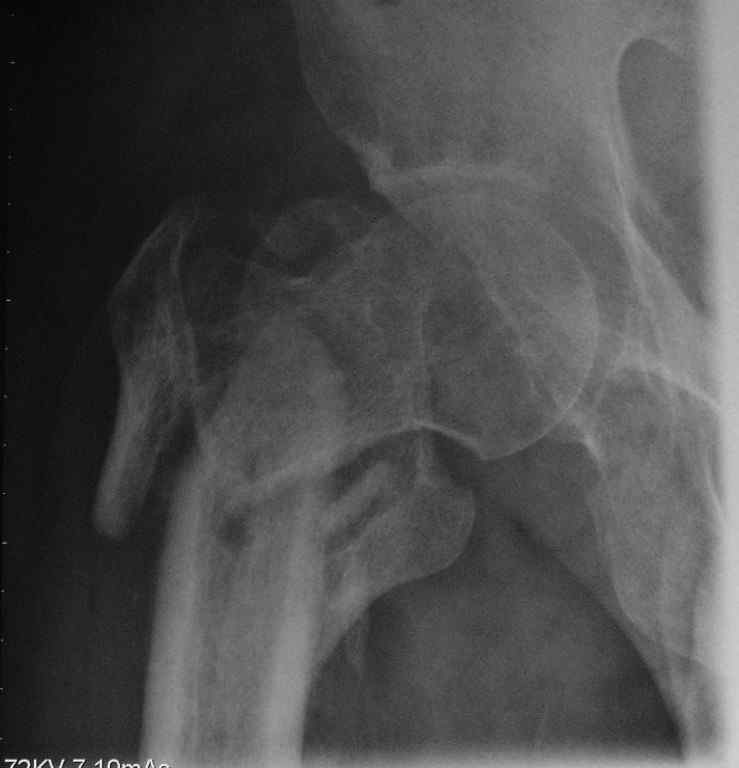

Пациент сорока лет с псевдартрозом правого бедра - исход оскольчатого чрезвертельного перелома с отрывом большого и малого вертелов. Поступил через 8 месяцев после травмы. По месту жительства лечили следующим образом: 2 месяца скелетное вытяжение, затем 2 месяца в кокситной повязке. После снятия гипса дали нагрузку. В настоящий момент имеется укорочение 6 см. Патологическая подвижность. По данным КТ - сращения нет, имеется аваскулярный некроз головки 2 стадии. В данном случае показано эндопротезирование тазобедренного сустава. Просим уважаемых коллег ответить на вопросы, которые возникли у нас по этому больному: 1. Имеет ли смысл выполнять первым этапом остеосинтез псевдартроза, учитывая, что нагрузка на сустав при наличии АНГБ противопоказана? 2. Возможно ли технически сразу выполнить эндопротезирование при наличии такого псевдартроза?

Форма головки сохранена, перелом, так скажем. не самый угрожающий в отношении ее "фатального" некроза.

Известно, что травматическая этиология в образовании Аваскулярного Некроза головки играет важную роль, но при чрезвертельных переломах трудно представить повреждение MCA, обеспечивающей около 80% кровоснабжения головки бедра.

Если имеются данные изотопного сканирования, кстати при начальных этапах это не всегда дает 100% результат, можно было бы выставить. А то на рентгенограмме не видно явлений, указывающих на АВН.

Лучше сделать МРТ, которая поможет аккуратно определить все стадии АВН.

Исследования убедят в правильности принятия решения, и у 40 летнего идти на ревизионный протез считаю немного агрессивным.